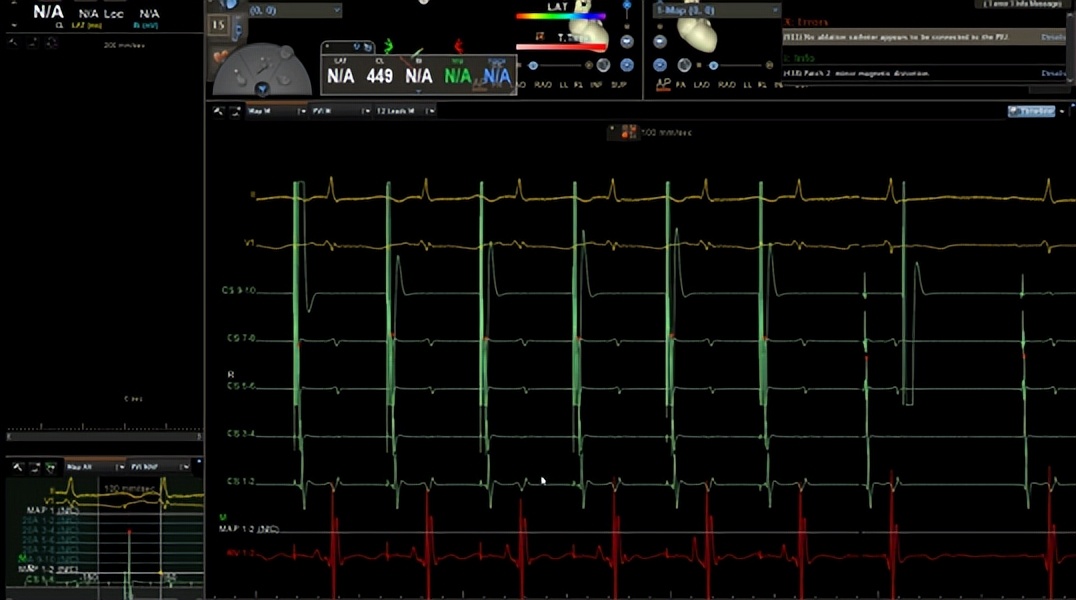

△诱发心律失常过程

△导管图

更让人振奋的是,同一天郑全主任团队还为78岁的许奶奶完成了阵发性室上心动过速射频消融术。“20年了,心跳一快起来就像要蹦出来,现在终于踏实了!”许奶奶术后难掩激动。

△ 消融治疗心律失常中